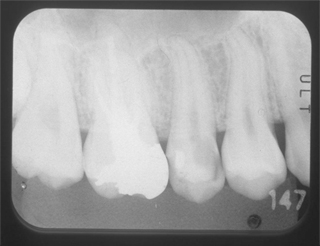

根管と歯のコントラストがはっきり見えません。

それは違う角度から見ると最終的なお薬が緊密に入っていないか、感染歯質を取りきれていないからです。

根のお掃除が不十分で、さらに最終的なお薬とのコントラストがはっきりしておらず、隙間だらけです